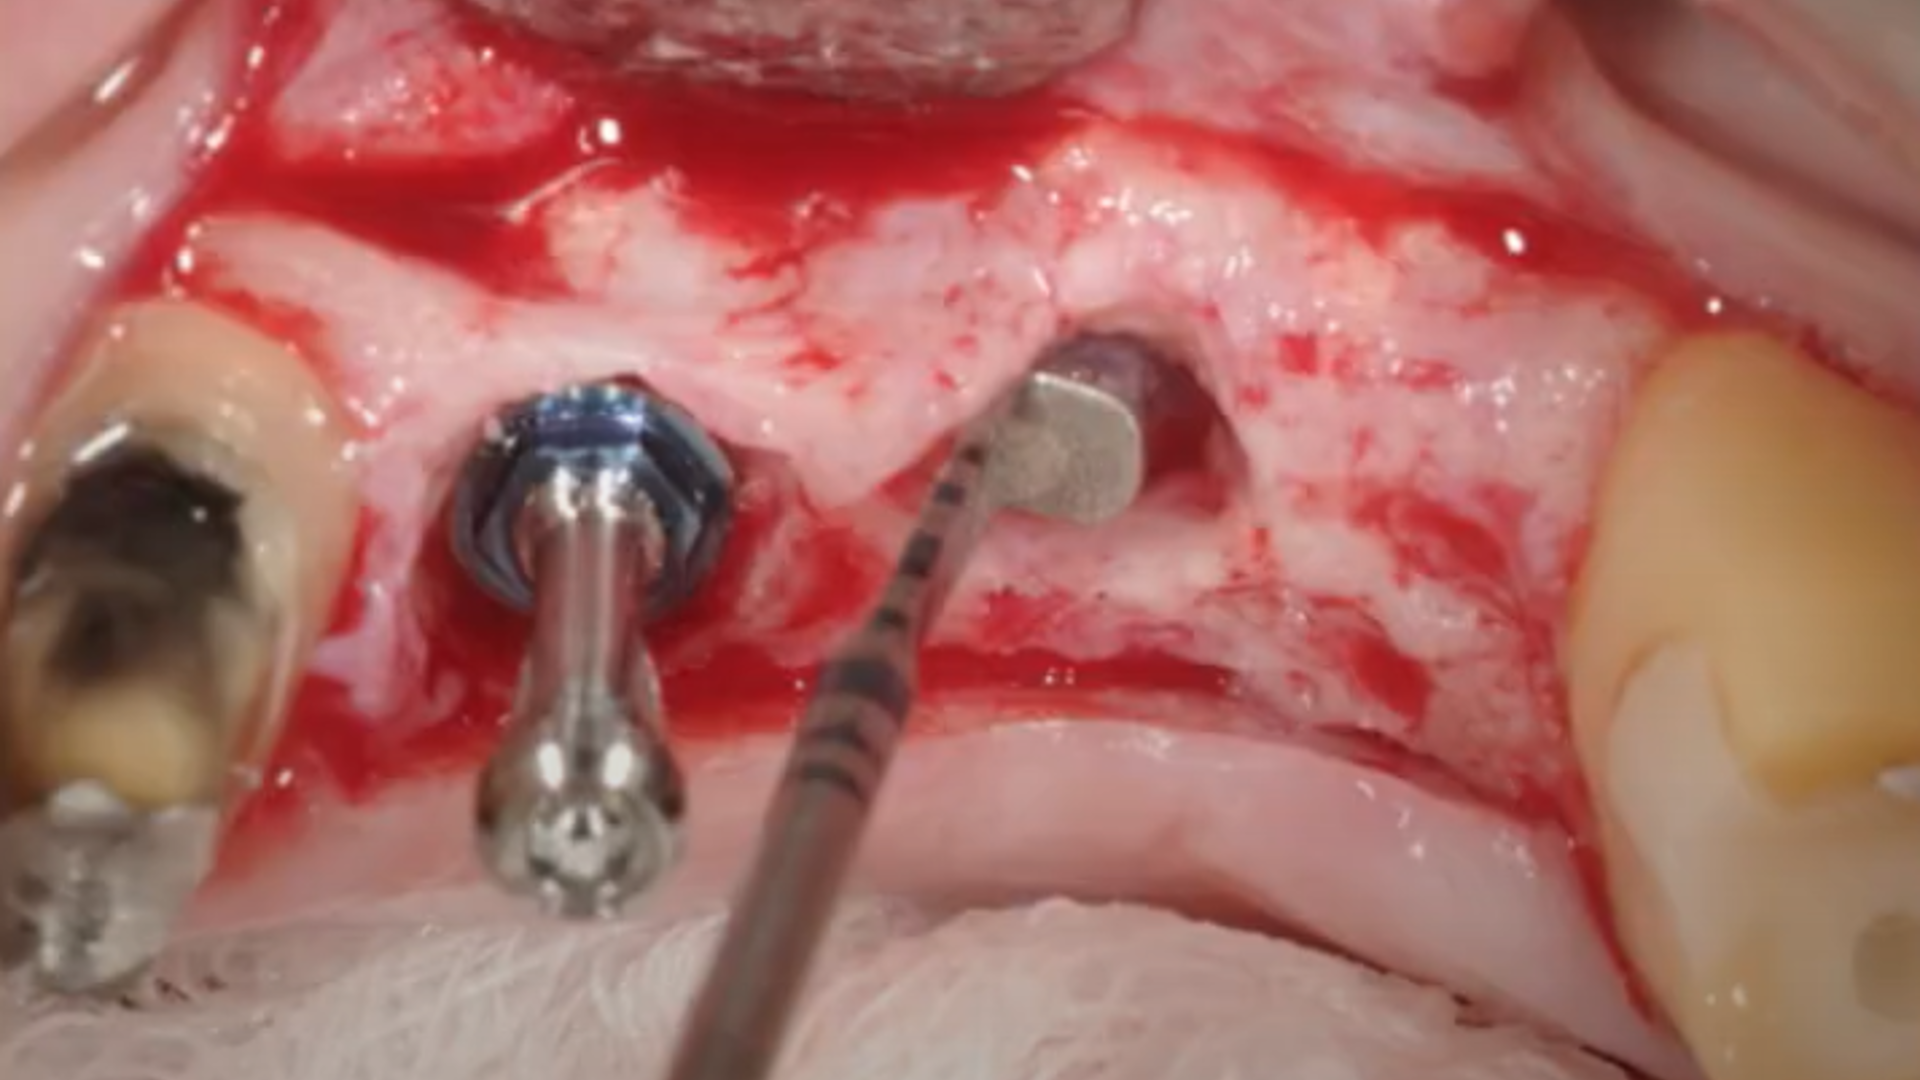

Evolution of sinus lift procedures: Piezo Surgery and Osseodensification

Example of different clinical cases: step-by-step surgical protocol

Osseodensification technique

Clinical video: Crestal sinus lift and multiple implant placement